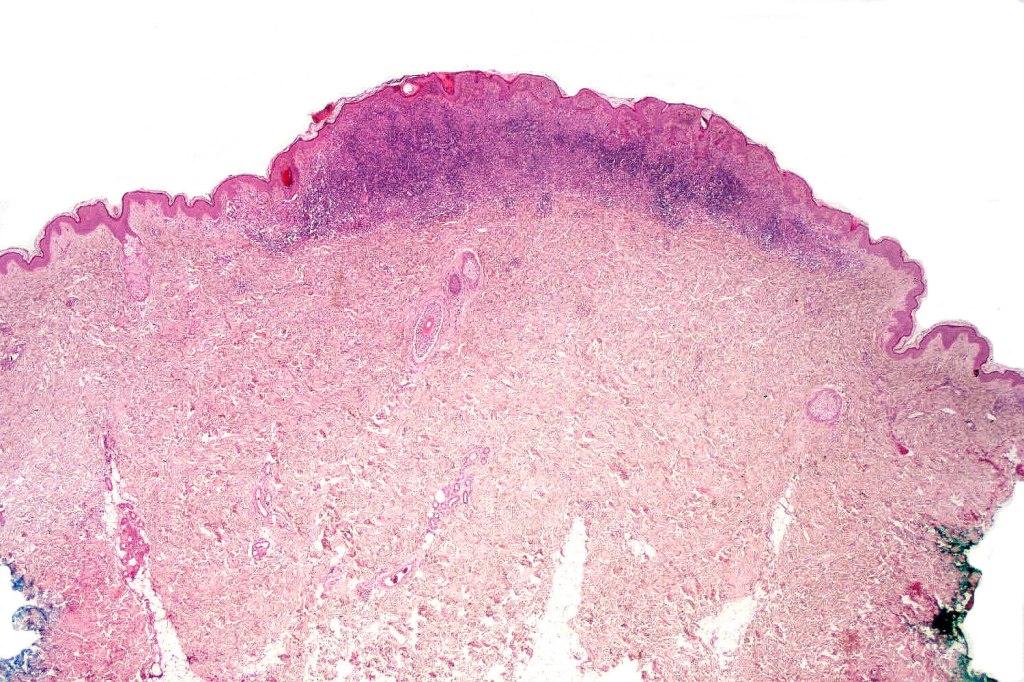

•Hyperkeratosis, & acanthosis sometimes present, otherwise epidermis of normal thickness

•Usually compound nevus with intense infiltration by lymphocytes, histiocytes and occasional plasma cells, in particularly florrid examples immunohistchemistry may be necessary to identify the nevus cells